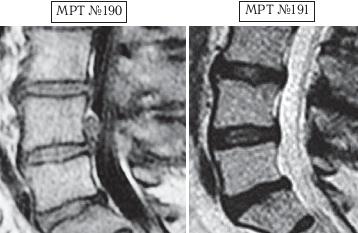

На МРТ № 188 наблюдается состояние поясничного отдела позвоночника после хирургического вмешательства: рецидив грыжи межпозвонкового диска в сегменте LV-SI краниальной миграцией секвестра, грыжи Шморля в сегментах LII—LIII и LIII—LIV стеноз спинномозгового канала.

На МРТ № 189 наблюдается состояние после лечения методом вертеброревитологии.